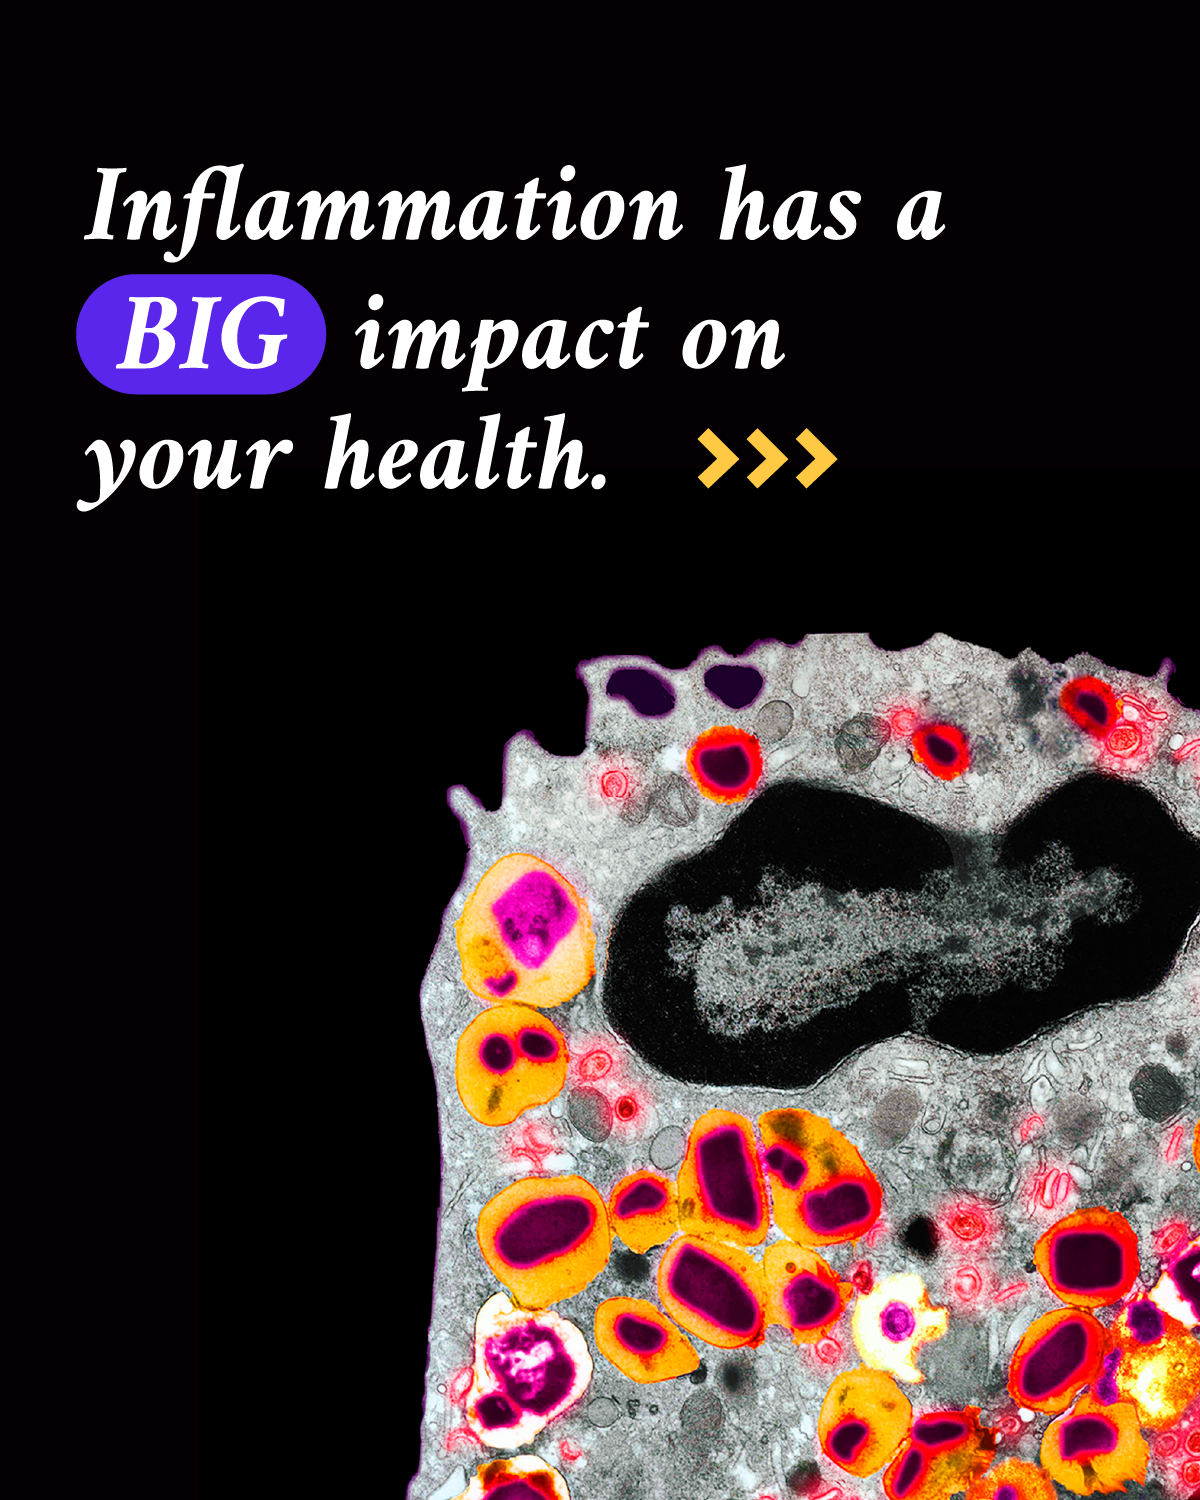

8. What happens to our cells and tissues when inflammation goes into overdrive?

Inflammation is our body’s first line of defense against injury or infection by harmful viruses, bacteria or other pathogens. It’s an important response from the immune system to try to minimize injury or infection and begin the healing process, but too much inflammation at the wrong place or time can become a problem.

About 50% of all deaths can be attributed to inflammation-related diseases — including cancer, heart disease and dementia. If scientists can watch the human immune system in action to see how our cells and tissues are impacted, they can figure out ways to control inflammation.